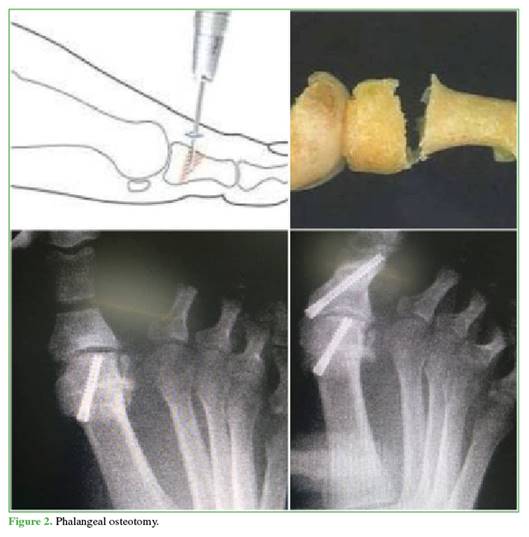

Osteotomy of the proximal phalanx. A 4 mm medial percutaneous incision is made over the proximal phalanx, 1 cm distal to the first MTP joint. Desperiostization is performed, followed by dorsal wedge osteotomy using a long Shannon burr. Osteoclastic closure is then achieved, and fixation is performed with a compression screw, placed from proximal to distal and from medial to lateral, without compromising the articular surface of the phalanx (Figure 2).